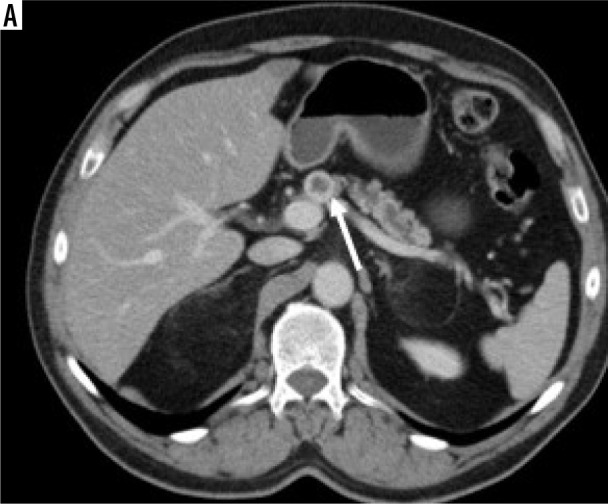

Results: There was no difference between the groups in terms of age, gender, tumour localisation, and internal structure (p = 0.23, p = 0.81, p = 0.19, and p = 0.94, respectively). Qualitative features significantly differed in terms of tumour margin feature, visual tumour density, presence of cystic component, and presence of necrosis (p = 0.01, p = 0.0001, p = 0.002, and p = 0.004, respectively). Tumour size, Tmden, Tmden/VPden, and Tmden/PanPden showed differences between groups (p = 0.0001, p = 0.002, p = 0.0001, p = 0.0001, respectively). The presence of cystic density in PDAC patients differed according to grade (p = 0.01).

Conclusions: While ill-defined irregular margins, hypodense visual tumour density, no cystic component, low value of Tmden, and low ratios of Tmden/VPden and Tmden/PanPden indicate PDAC, regular margins, iso-or hyperdense visual tumour density, cystic component, high value of Tmden, and high ratios of Tmden/VPden and Tmden/PanPden indicate PNET. SC can be differentiated from them by containing necrosis and reaching larger sizes. The presence of a cystic component in PDAC patients indicates high grade.